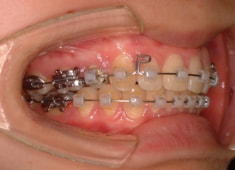

治療開始時

治療開始から1年7ヶ月後